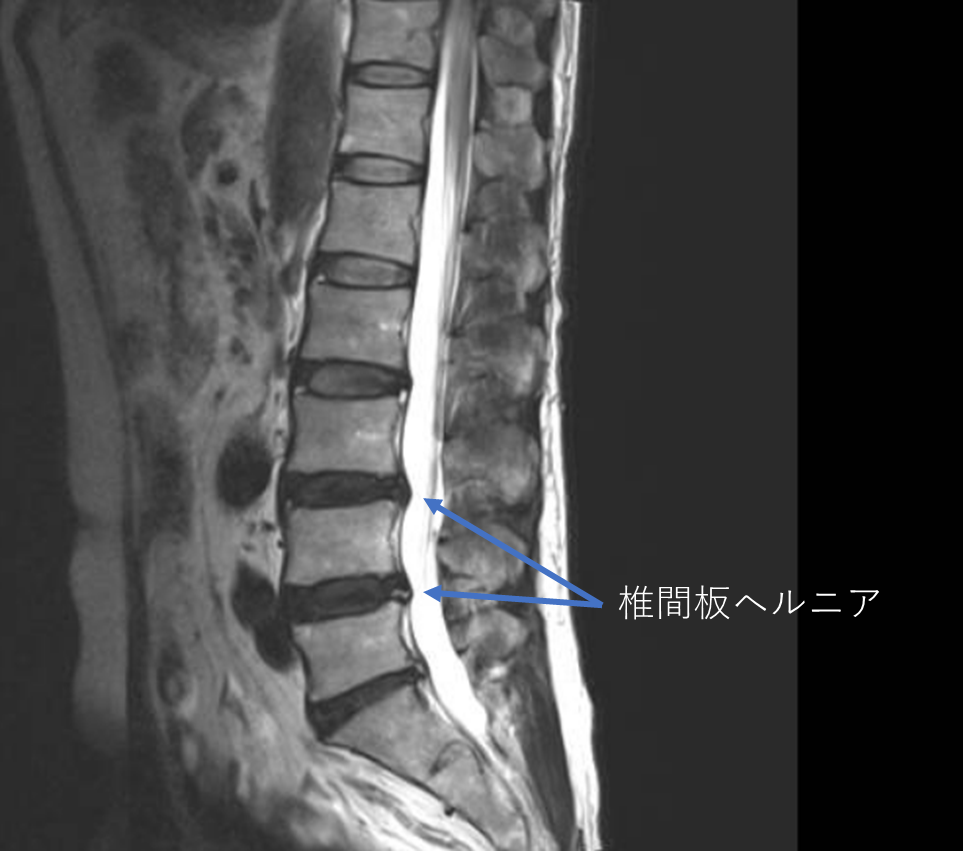

画像及び所見について

- L3/4,4/5-椎間板ヘルニア

- L2/3,3/4,4/5,5/s-椎間板変性

- L2/3,3/4,4/5-線維輪断裂

以上の事が画像上認められます。

・L3/4,4/5-左椎間板ヘルニアを認め、主症状の原因の可能性が高い

・L2/3-線維輪断裂を認め、症状の原因の可能性がある